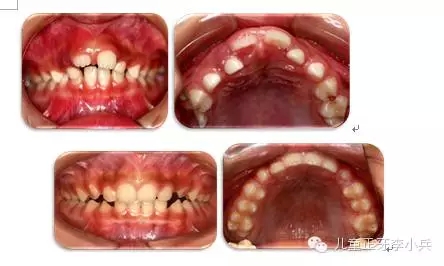

3. 牙槽骨早期塑形矯治:良好的咬合必須是上下頜骨大小位置正常、上下牙大小排列正常,以及上下牙弓的大小與形態(tài)協(xié)調(diào)。臨床功能矯形可調(diào)整上下頜骨大小與位置的不調(diào);臨床正畸治療可矯治牙齒排列異常。而上下牙槽骨的大小形態(tài)不協(xié)調(diào)的早期矯治就是牙槽骨的早期塑形。牙槽骨的發(fā)育包含牙槽骨長(zhǎng)、寬、高三項(xiàng)的發(fā)育,常見(jiàn)的牙槽骨發(fā)育異常是寬度的不足,形成功能性下頜后縮及牙列擁擠。早期的牙槽骨括弓能打開(kāi)腭中縫,擴(kuò)大牙弓寬度,增加牙弓周徑,避免功能性II類(lèi)及擁擠的發(fā)生。(圖4,早期牙槽骨塑形矯治)

42.webp.jpg

圖4 上頜牙弓狹窄,牙槽骨擴(kuò)弓塑形促進(jìn)上下牙弓正常發(fā)育;